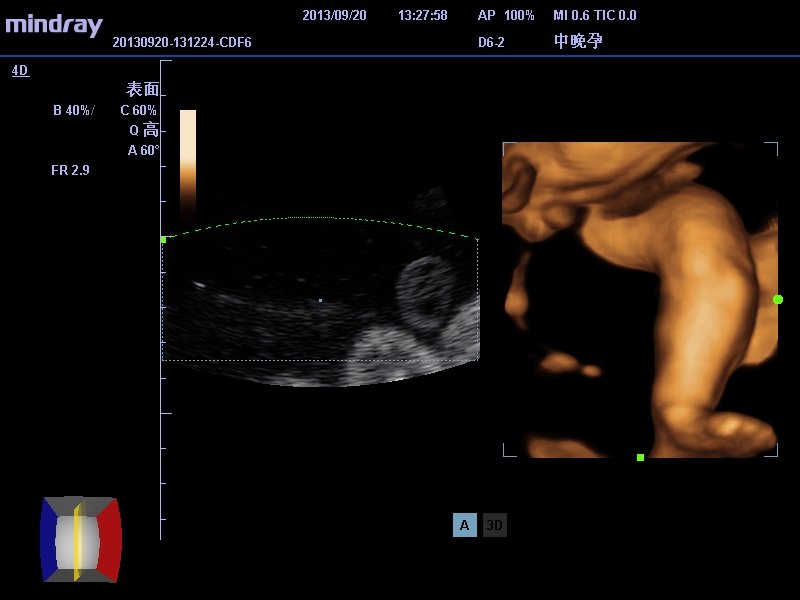

有医生可以帮我看看做四维彩超拍到了像是男孩的生殖器

请医生帮我看看这是男性的生殖器吗   是不是男孩啊

不得不说这技术看着让人揪心,二维只能肯定脐带影像,三维像是腿的部分,至于你说的生殖报揭器没法认定。再说现在禁细沃贵止鉴定胎儿性别,男孩女孩不一样好么?何况超声所见也有假阴性和假阳性,只能命竖生下来了才最终揭晓。